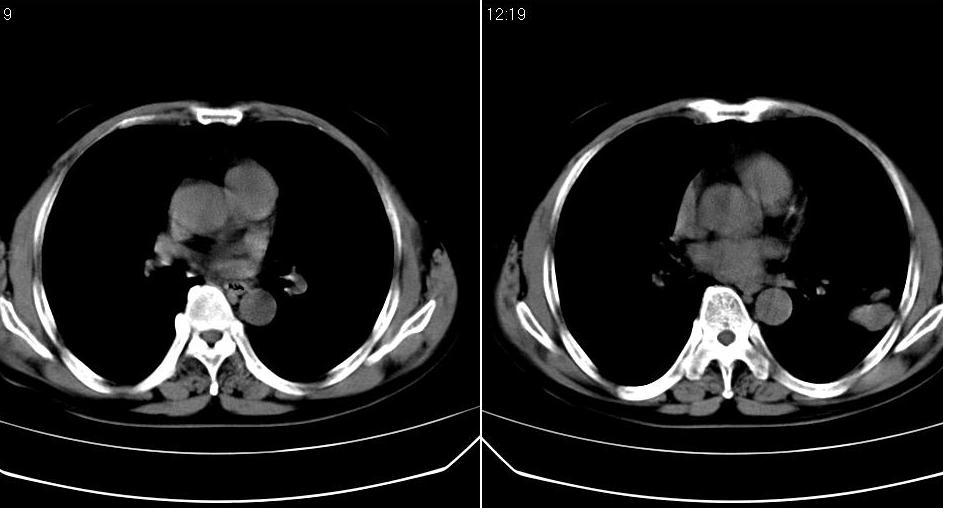

标题: CT19131:男 60岁,咳嗽,喀痰,胸闷,有吸烟史,胸部CT平扫 [打印本页]

男 60岁,咳嗽,喀痰,胸闷,有吸烟史,正常图片未上传,请谅解。

左肺周围型肺癌。

左肺肿块有分叶、有毛刺,符合周围型肺癌。

考虑左肺下叶周围型肺癌可能性大。

分叶状肿块,有毛刺,有晕,有粗纹理直通肺门,支持考虑周围型肺癌